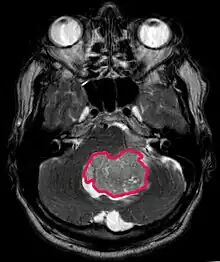

La tomodensitométrie (TDM) et L'imagerie par résonance magnétique (IRM) peuvent détecter efficacement une néoplasie dans le cerveau. L'IRM est plus sensible que la TDM pour identifier les lésions, mais présente des contre- indications pour les patients porteurs de stimulateurs cardiaques, de prothèses incompatibles, de clips métalliques et contre-indications. La TDM reste la méthode de choix pour détecter les calcifications au sein des lésions ou les érosions osseuses de la calotte ou de base du crâne. L'utilisation d' agents de contraste, iodés dans le cas du scanner et paramagnétiques (gadolinium) dans le cas de l'IRM, permet l'acquisition d'informations sur la vascularisation et l'intégrité de la barrière hémato-encéphalique, une meilleure définition de la tumeur tumorale par rapport à l' œdème environnant et à la génération d' hypothèses sur le degré de malignité. L'examen radiologique permet également d'évaluer les effets mécaniques et les modifications importantes des structures cérébrales résultant de la tumeur, telles que l' hydrocéphalie et les hernies, dont les effets peuvent être fatals. Enfin, en préparation à la chirurgie, ce diagnostic peut être utilisé pour déterminer la localisation de la lésion ou l'infiltration de la tumeur dans des zones vitales du cerveau. À cette fin, l'IRM est plus efficace que la tomodensitométrie car elle peut fournir des images en trois dimensions.

Sur-L'IRM montre une tumeur intracrânienne comme une lésion massive qui peut devenir plus luminescente après utilisation du produit de contraste. Cependant, il y a toujours une anomalie de signal dans -L'imagerie par résonance magnétique, qui indique la présence d'une néoplasie ou d'un œdème vasogénique. Habituellement, une luminescence accrue (amélioration du contraste) indique une tumeur d'un grade supérieur de malignité. Un anneau de contraste est caractéristique du glioblastome, avec la partie luminescente correspondant à la partie vitale de la tumeur maligne, et la plus foncée - zone hypointense correspondant à une nécrose tissulaire.

L'IRM montre généralement une lésion de contraste massive impliquant le cervelet. Comme mentionné ci-dessus, le médulloblastome a une forte propension à infiltrer localement les leptoméninges ainsi qu'à se propager à travers l'espace sous-arachnoïdien, impliquant les ventricules, la convexité cérébrale et les surfaces leptoméningées de la colonne vertébrale. Par conséquent, il est nécessaire de mettre en résonance tout l'axe crânio-spinal.

Les patients souffrent d'une variété de symptômes caractéristiques d'une lésion massive focale ou multifocale. L'IRM montre généralement des tumeurs avec un rehaussement de contraste homogène au sein de la substance blanche périventriculaire profonde. La multifocalité et le rehaussement inhomogène sont typiques des patients dont le système immunitaire est affaibli. L'analyse du lymphome du SNC est extrêmement importante dans le diagnostic différentiel de la néoplasie cérébrale. Il est à noter que l'administration de corticoïdes peut entraîner la disparition complète du rehaussement, rendant difficile le diagnostic des lésions. Par conséquent, si un lymphome du SNC doit être pris en compte dans le diagnostic différentiel, les corticoïdes doivent être évités à moins que l'effet de masse ne provoque un problème grave et immédiat chez le patient.